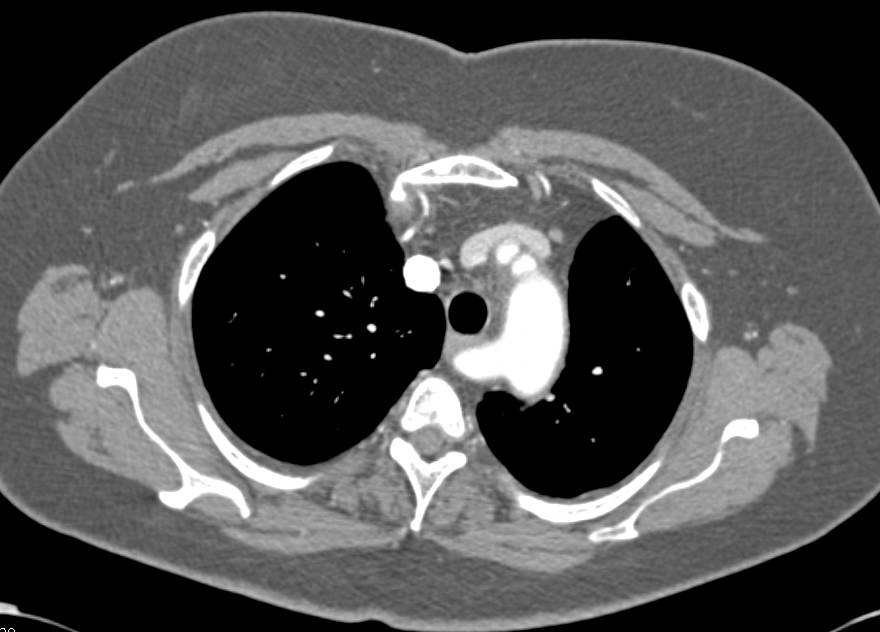

Marfan Syndrome with Dilated Sinus of Valsalva